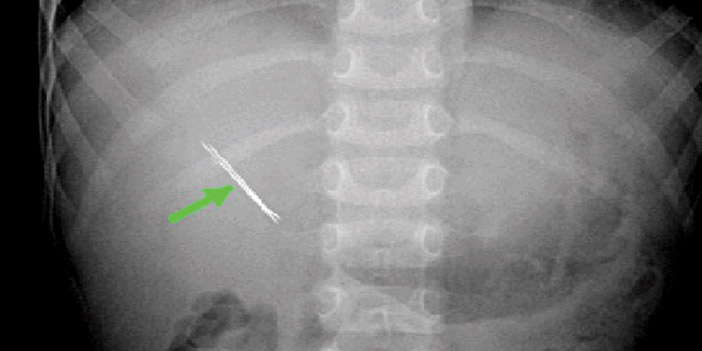

هذا، ورغم الفائدة الكبيرة للدبابيس فهي أحياناًً وبسبب الإهمال تتسبب في وقوع حوادث بعضها يكون مميتاً.. فجميع مستشفيات العالم تشهد بين فترة وأخرى وصول حالة إسعافية نتيجة لتعرض أحد الأطفال لابتلاع دبوس. أو سيدة كانت تخيط ملابس وكانت تضع في فمها دبابيس لحفظها، فاذا بها تبتلع عدداً منها.. أو أحد كبار السن داس على دبوس كان مغروساً في سجادة فدخل في قدمه.. واحتاج لعملية جراحية دقيقة لإخراجه. وكم دبوس تسبب في التهاب قدم إنسان ومع الأيام التهب وشكل خطورة كبيرة وعلى الأخص مرضى السكري!… وكم من فتاة وخلال لحظة غفلة ابتلعت دبوساً خلال ثوانٍ. وهذه حكاية طفل كان يعاني من آلام مبرحة ومعاناة والآن استمرت لمدة ثلاثة أشهر، إضافة إلى قلق وخوف والديه مما يعانيه طفلهم العزيز والذي كان عمره أربع سنوات. ومع أنه كان قد عرض على أكثر من طبيب ووصف له أدوية وعلاجات مختلفة من المضادات الحيوية، لكن ما زال طفلهم يعاني بل ازدات الحمى والقشعريرة في جسمه وآلام حادة في بطنه الجهة اليمنى وبين أضلاعه ووركه، وبعد نقله للمستشفى، وعمل الأشعة له اكتشف وجود «دبوس». واعترف الطفل أنه ابتلع «الدبوس» الذي كان قد اخترق كليته، وكان لابد من استخراجه جراحياً، وهذا ما حدث.. وهذه الحادثة حدثت في بلادنا. والعملية أجريت بنجاح في مستشفى بجدة..